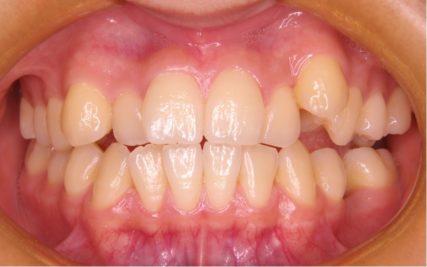

- 治療前

- 上下とも前歯のスペース不足が認められた。歯のサイズと顎の幅とのバランスが不調和な事が原因の1つとして考えられる。

- 治療後

- 前歯部のでこぼこが解消され、正常咬合を獲得する事が出来た。又、歯科矯正用アンカースクリューを用いる事で抜歯スペースを有効に利用できた。